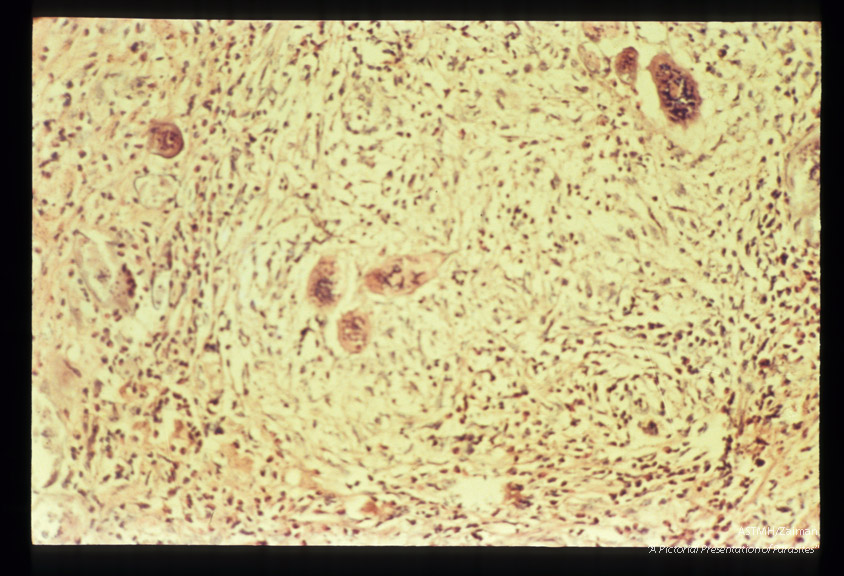

Adults and ova in human testicle.

Schistosoma haematobium

Description: Adults and ova in human testicle.